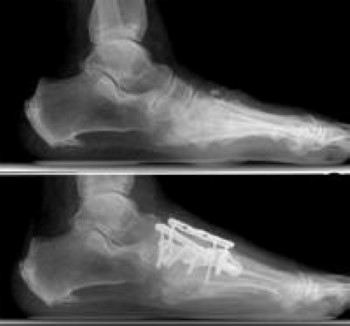

With RA, the ligaments that support the midfoot become weakened and the arch collapses.

- With loss of the arch, the foot commonly collapses and the front of the foot points outward.

- RA also damages the cartilage, causing arthritic pain that is present with or without shoes.

- Over time, the shape of the foot can change because the structures that support it degenerate. This can create a large bony prominence (bump) on the arch. All of these changes in the shape of the foot can make it very difficult to wear shoes.

Fusion is the most reliable surgical method to treat RA of the midfoot joints. If the shape of the foot is not normal, surgery is designed to help restore the arch and minimize the prominences (bumps) on the foot.

Although the foot cannot be returned to a normal shape, the goals are to reduce pain in the foot and improve the potential for the patient to wear more normal shoes.